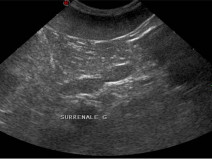

• Échographie de la rate, des surrénales et des noeuds lymphatiques / TP ponctions échoguidées

Public visé : La formation est ouverte aux docteurs vétérinaires qui souhaitent offrir au sein des établissements de soin vétérinaire des prestations de qualité accrue en échographie des animaux de compagnie

Prérequis : Être docteur vétérinaire. évoluer dans une structure de soins vétérinaires disposant d’un échographe ou vouée à en disposer dans un...

Du 21 au 22 octobre 2017

Mérignac (33700)

Imagerie Médicale

G.E.I.M.

217